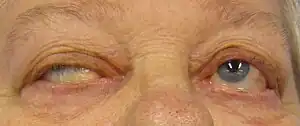

| Eye deviation and a drooping eyelid in a person with myasthenia gravis trying to open her eyes | |

Myasthenia gravis (MG) is a long-term neuromuscular disease that leads to varying degrees of skeletal muscle weakness.[1] The most commonly affected muscles are those of the eyes, face, and swallowing.[1] It can result in double vision, drooping eyelids, trouble talking, and trouble walking.[1] Onset can be sudden.[1] Those affected often have a large thymus or develop a thymoma.[1]

The initial, main symptom in MG is painless weakness of specific muscles, not fatigue.[11] The muscle weakness becomes progressively worse during periods of physical activity and improves after periods of rest. Typically, the weakness and fatigue are worse toward the end of the day.[12] MG generally starts with ocular (eye) weakness; it might then progress to a more severe generalized form, characterized by weakness in the extremities or in muscles that govern basic life functions.[13]

Eyes

In about two-thirds of individuals, the initial symptom of MG is related to the muscles around the eye.[11] There may be eyelid drooping (ptosis due to weakness of levator palpebrae superioris)[14] and double vision (diplopia,[11] due to weakness of the extraocular muscles).[12] Eye symptoms tend to get worse when watching television, reading, or driving, particularly in bright conditions.[11] Consequently, some affected individuals choose to wear sunglasses.[11] The term "ocular myasthenia gravis" describes a subtype of MG where muscle weakness is confined to the eyes, i.e. extraocular muscles, levator palpebrae superioris, and orbicularis oculi.[14] Typically, this subtype evolves into generalized MG, usually after a few years.[14]